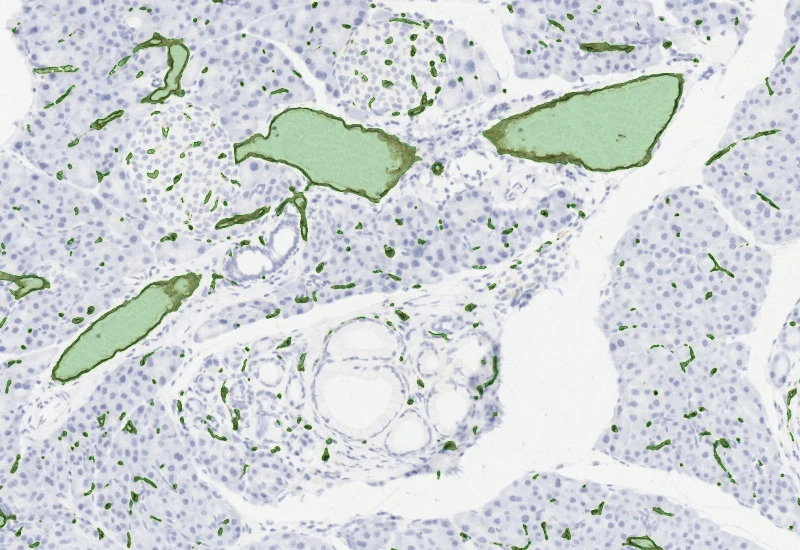

The Angio Sirius Red App detects collagen based on Sirius Red staining as well as blood vessels. As outcome the APP outputs the area of Sirius Red stained collagen as well as the number of detected vessels.

vessel detection

Collagen detection